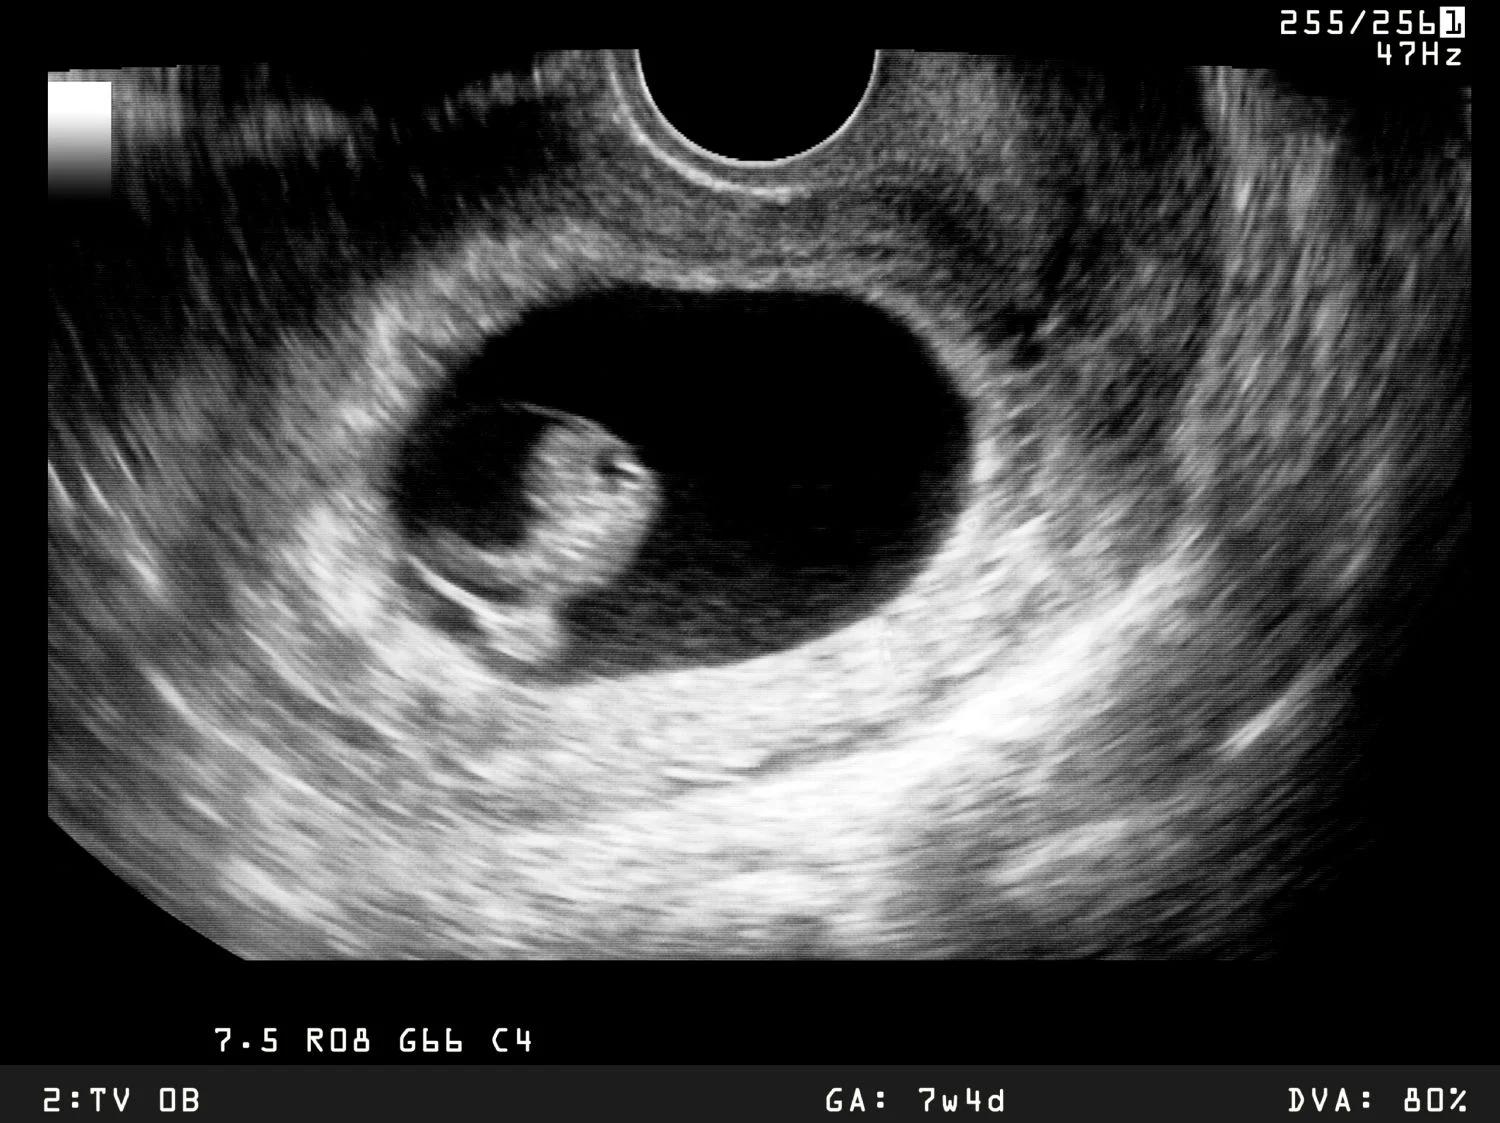

Die Sonographie wird in der Regel in drei verschiedenen Phasen der Schwangerschaft durchgeführt:

- Screening: In der bis 1Schwangerschaftswoche. Dieses Screening dient dazu, die Schwangerschaft zu bestätigen, die Größe des Embryos zu bestimmen und die Entwicklung des Herzens zu kontrollieren.